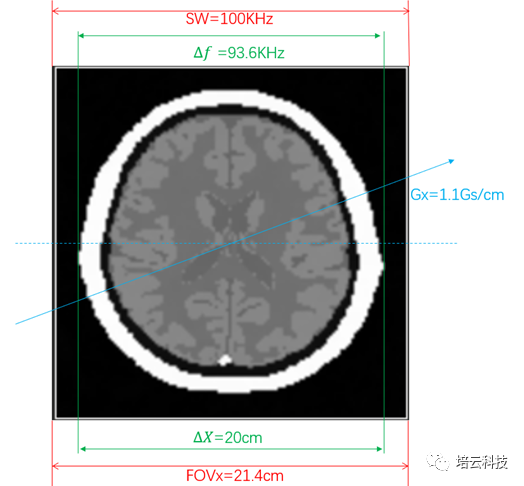

仿真实验平台上,当采用默认参数,Gx=Gy=1.1Gs/cm时,采集的k空间和重建图像如图1所示:

图1 采集的k空间和重建图像

由于MRI图像是空间频率域,即空间和频率是等效的,二者之间由系数K进行转换:f=k C;f为频率,C为空间坐标位置。具体到二维平面,横向位置有fx=kxX;纵向有fy=kyY。其中,kx=𝛾Gx;ky=𝛾Gy。因此SW=100KHz的视野频率范围,在Gx=1.1Gs/cm的梯度场下,选定的视野空间范围为:FOVx=SW/𝛾Gx≈21.4cm(注1T=10000Gs)。

人脑模型的横向尺寸为20cm,在1.1Gs/cm的梯度场下,左右两侧的频率差为:Δf =𝛾GxΔX≈93.6kHz,因此脑模型图像在横向上占视野的比例约为93.6kHz/100kHz=93.6%。频率和位置映射关系如图2所示。由此也进一步说明,磁共振图像是空间频率域的信号(空间和频率一体),原始K数据是时间域的。

图2 频率编码方向的频率和位置映射关系